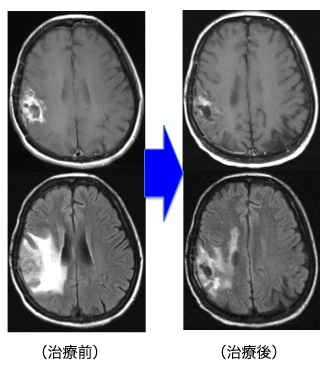

前述の如く、神経膠腫(グリオーマ)は、一部の腫瘍を除き手術のみで完治させることはできません。従って、術後に放射線治療と化学療法は不可欠です。手術後にどのような補助療法を行なうかは施設により意見が分かれるところです。しかし最近では欧米を中心に、複数の施設による大規模で多数の患者に対して信頼性の高い試験が行われております。我々はそれらの最新結果を基にして十分な説明を行い、納得・同意を得た上で補助療法を決定しております。放射線治療を主軸に化学療法を併用する標準治療が原則ですが、特に化学療法剤であるテモゾロマイド (TMZ)は経口投与の可能な薬剤であり、副作用が少なく簡便に治療ができます。当科でも従来の化学療法を凌駕する治療成績の向上がみられています。

Grade 4(膠芽腫):手術+放射線治療+化学療法(TMZ±Bev(アバスチン))±交流電場腫瘍治療(NovoTTF)

放射線治療に化学療法を併用します。(治療期間は6週間ですが、高齢者の場合は放射線治療を3週間に短縮して行うこともあります。その場合でもTMZは6週間使用します。)